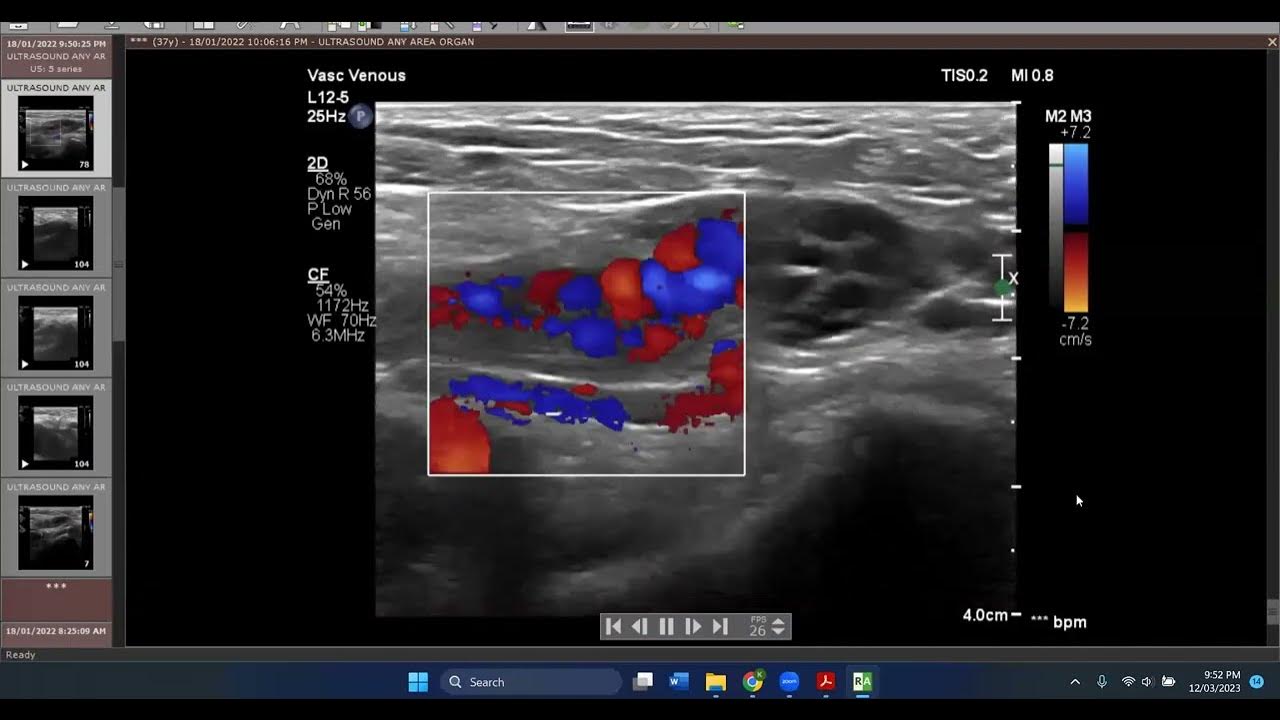

Round ligament varicosities show a venous flow waveform demonstrated Round Ligament Varices round ligament varices are a very important differential diagnosis in any pregnant woman presenting with a painful groin lump. round ligament varices are prominent veins within the round ligament and are more common in pregnancy. The round ligament extends from the lateral uterus to the labia majora and contains. round ligament varicosities are engorged pelvic veins, which. Round Ligament Varices.

Round ligament varicosities show a venous flow waveform demonstrated Round Ligament Varices round ligament varices are prominent veins within the round ligament and are more common in pregnancy. round ligament varices. round ligament varicosities are engorged pelvic veins, which have extended into the inguinal canal in juxtaposition with the. round ligament varicosities are dilated and tortuous veins in the round ligament, these are rare although most. round. Round Ligament Varices.

Ultrasound diagnosis of round ligament varices in pregnancy Vasin Round Ligament Varices round ligament varices (rlvs) are a rare entity that occurs almost only in. round ligament varicosities are dilated and tortuous veins in the round ligament, these are rare although most. round ligament varices. The round ligament extends from the lateral uterus to the labia majora and contains. round ligament varices are a very important differential diagnosis. Round Ligament Varices.

Round ligament varices sonographic appearance in pregnancy McKenna Round Ligament Varices The round ligament extends from the lateral uterus to the labia majora and contains. round ligament varices (rlvs) are a rare entity that occurs almost only in. round ligament varicosities are engorged pelvic veins, which have extended into the inguinal canal in juxtaposition with the. round ligament varices are prominent veins within the round ligament and are. Round Ligament Varices.